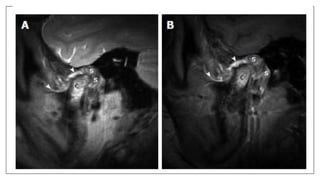

Normal anatomy